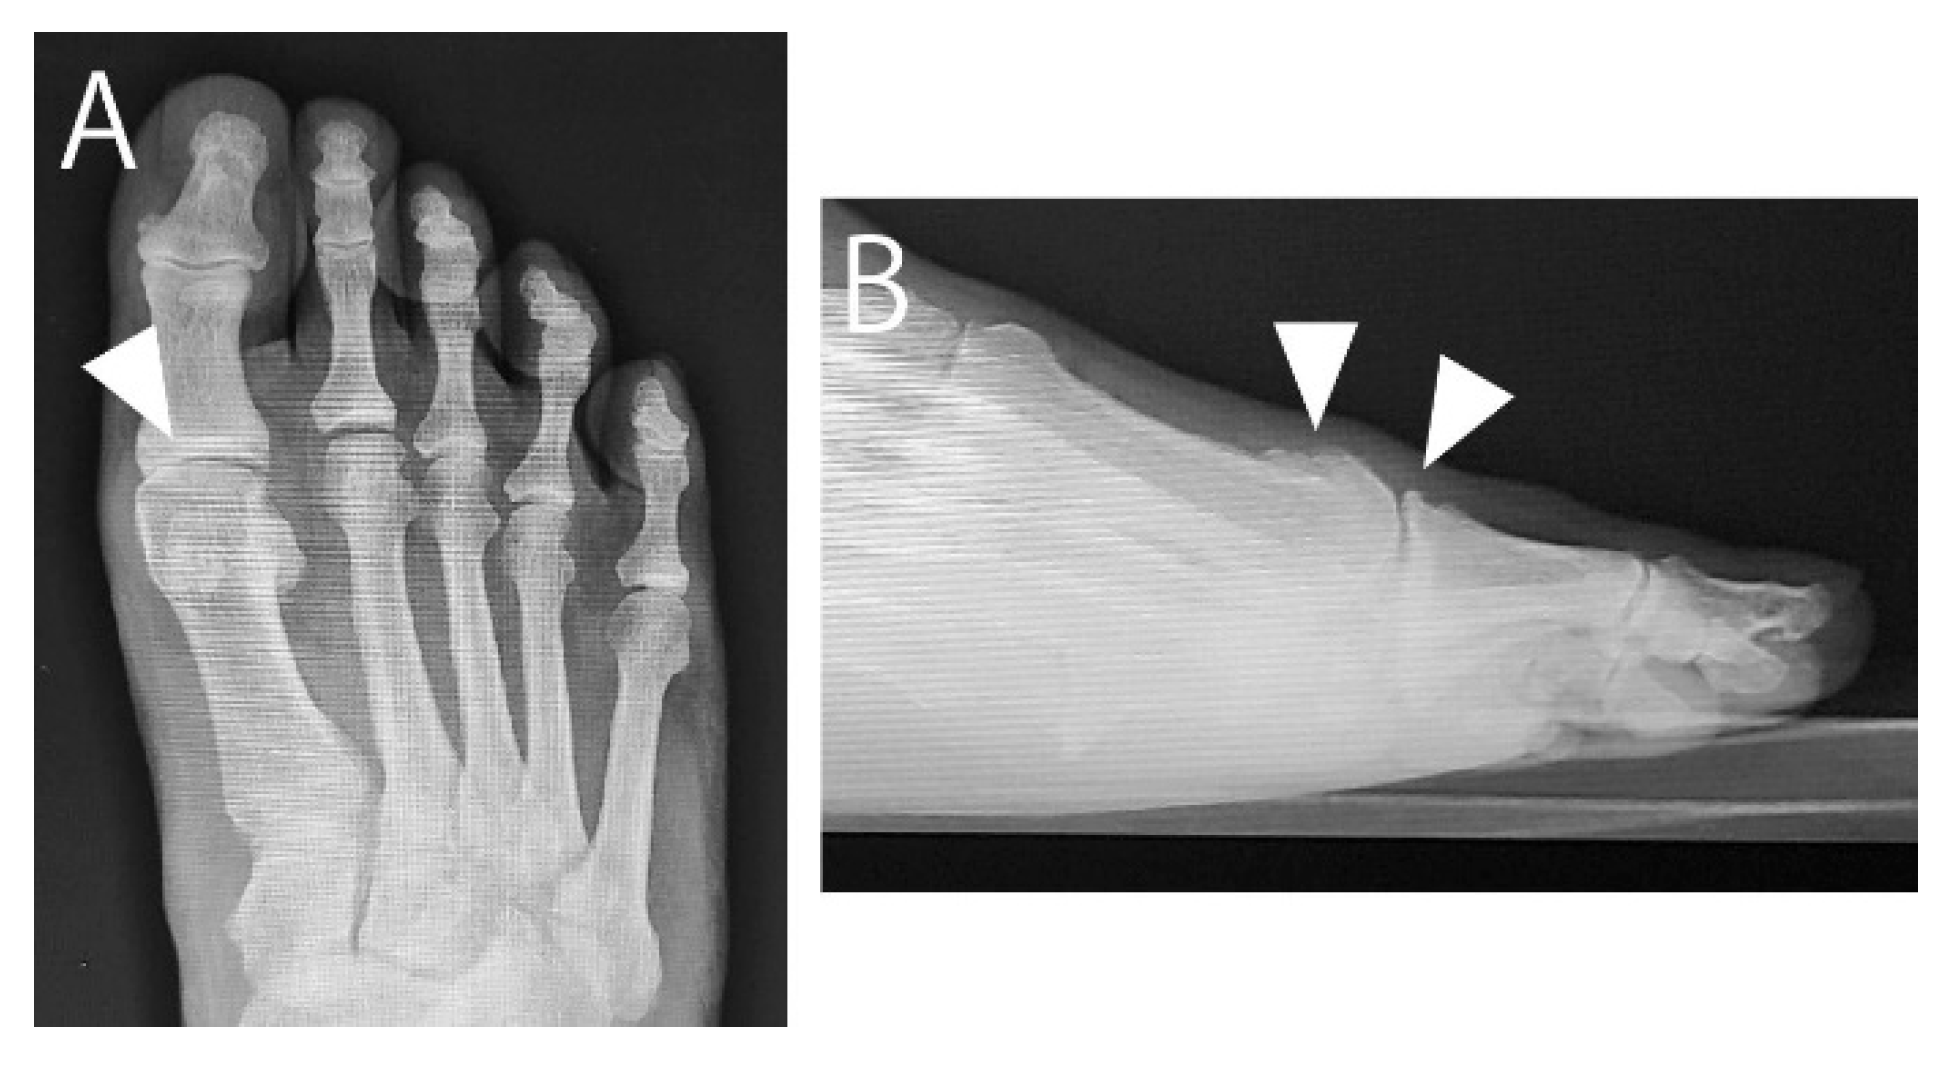

In April 2015, a 73-year-old male with HR of the right foot sought consult after unsatisfactory conservative management of 1 year at a nearby clinic. He complained of a painful bony prominence, limited dorsiflexion, and pain during walking at the first MTP joint. The MTP joint was swollen, and a bony prominence at the dorsal joint was palpable. The passive dorsiflexion angle was 55°. The visual analog scale (VAS) score for pain during walking was 70, and the Japanese Society for Surgery of the Foot (JSSF) score [8,9] was 57. Radiographs showed a narrowed MTP joint space. Computed tomography revealed spur growth at the distal portion of the first metatarsal and the proximal portion of the proximal phalanx (Figure 1 and Figure 2). The patient opted for arthroscopic surgery; therefore, we proposed an arthroscopic cheilectomy and, if the improvement in dorsiflexion is insufficient, additional plantar soft tissue release can be performed.

Figure 1. Preoperative radiographs. (A) Weight-bearing anteroposterior image showing the narrow first metatarsophalangeal joint space (arrowhead). (B) Weight-bearing lateral image showing dorsal spurs on the metatarsal head and the proximal phalanx (arrowheads).